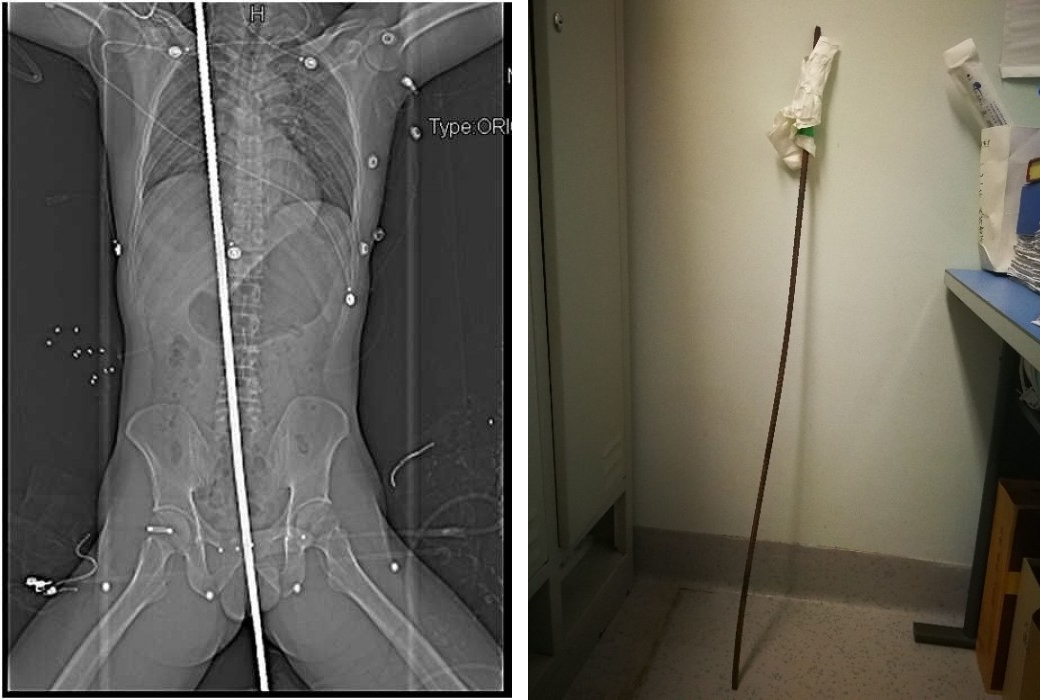

그 아래에는 지름 1cm 정도 되는 철근이 수직 방향으로 설치되어 있었는데 그곳으로 떨어지면서 철근이 항문 부근을 찌르고 몸통을 관통하여 오른쪽 어깨 부근까지 이르렀습니다.

남성은 곧장 성도시내에 있는 사천대학 화서병원으로 긴급 이송되었고 누가 봐도 지극히 심각한 사태의 이 환자에 대하여 의사들은 즉시 엑스레이 촬영 등을 실시했는데 다행히 체내에서 대출혈이 발생한 징후는 보이지 않았습니다.

의사들은 손상된 폐와 간의 일부를 절제하고 손상된 소장을 꿰맨 후 두께 1cm, 길이 1.2m의 철근을 뽑아냈다고 합니다.

좌측 엑스레이 사진이 철근이 항문에서 어깨까지 관통하여 박혀진 사진이고 우측은 몸에서 빼낸 철근.